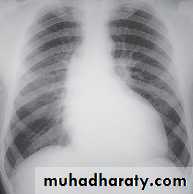

Radiology of the Heart

Chest X-ray: Postero-anterior view (PA view):Size of the heart

Shape of the heart

Specific chamber enlargement

Status of the pulmonary circulation

Cardiac size:Cardio-thoracic ratio (CTR):

Normally < 0.5

Enlargement of the heart (cardiomegaly):

LV dilatation and dysfunction

Pericardial effusion

Left atrial enlargement:Straight heart border (LA appendage)

Widening of the carinal angle

Double contour of the right heart border

LV enlargement:Enlarged cardiac silhouette

Prominent left heart border

RV enlargement:Cardiomegaly

Straightening of the left heart border

Apex displaced upwards

Right atrial enlargement:

Prominence of the right border of the heart

Lung fields:Congestion & edema in patients with left heart failure

Increased blood flow (prominent arteries and veins) in shunt lesions

Oligemic lungs in pulmonary stenosis

Pleural effusions in advanced heart failure